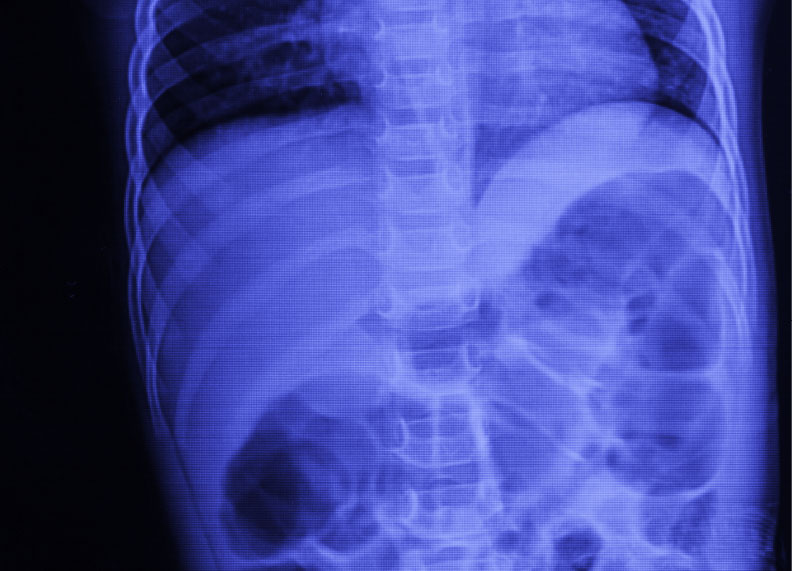

腹部レントゲン

おなかにX線を照射して、疾患・病変を発見するために行われるレントゲン検査の一種です。

おなかの痛みが主訴で検査をします。

腸閉塞、消化管穿孔、腎結石、尿路結石などの状態を調べる為に用いられます。

検査に苦痛や辛さはありません。

腹部レントゲン検査について

肛門からバリウムを入れて検査する「大腸レントゲン検査」とは違いますので苦痛はありません。

検査目的によって立った状態と仰向けに寝た状態で撮影します。

「息を吸って、吐いて、止めて下さい」という胸のレントゲンの時とは違う合図をします。

息を吐くことにより肝臓や腎臓などが観察しやすくなるためです。